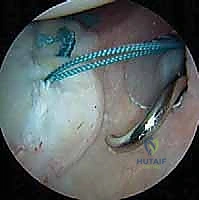

ترقيع الغضروف العظمي الذاتي: استعادة الحياة لمفصل الركبة مع الأستاذ الدكتور محمد هطيف

استعيدوا صحة ركبكم! تعرفوا على ترقيع الغضروف العظمي الذاتي لعلاج تلف الغضروف مع الأستاذ الدكتور محمد هطيف في صنعاء. حلول متقدمة لآلام الركب…